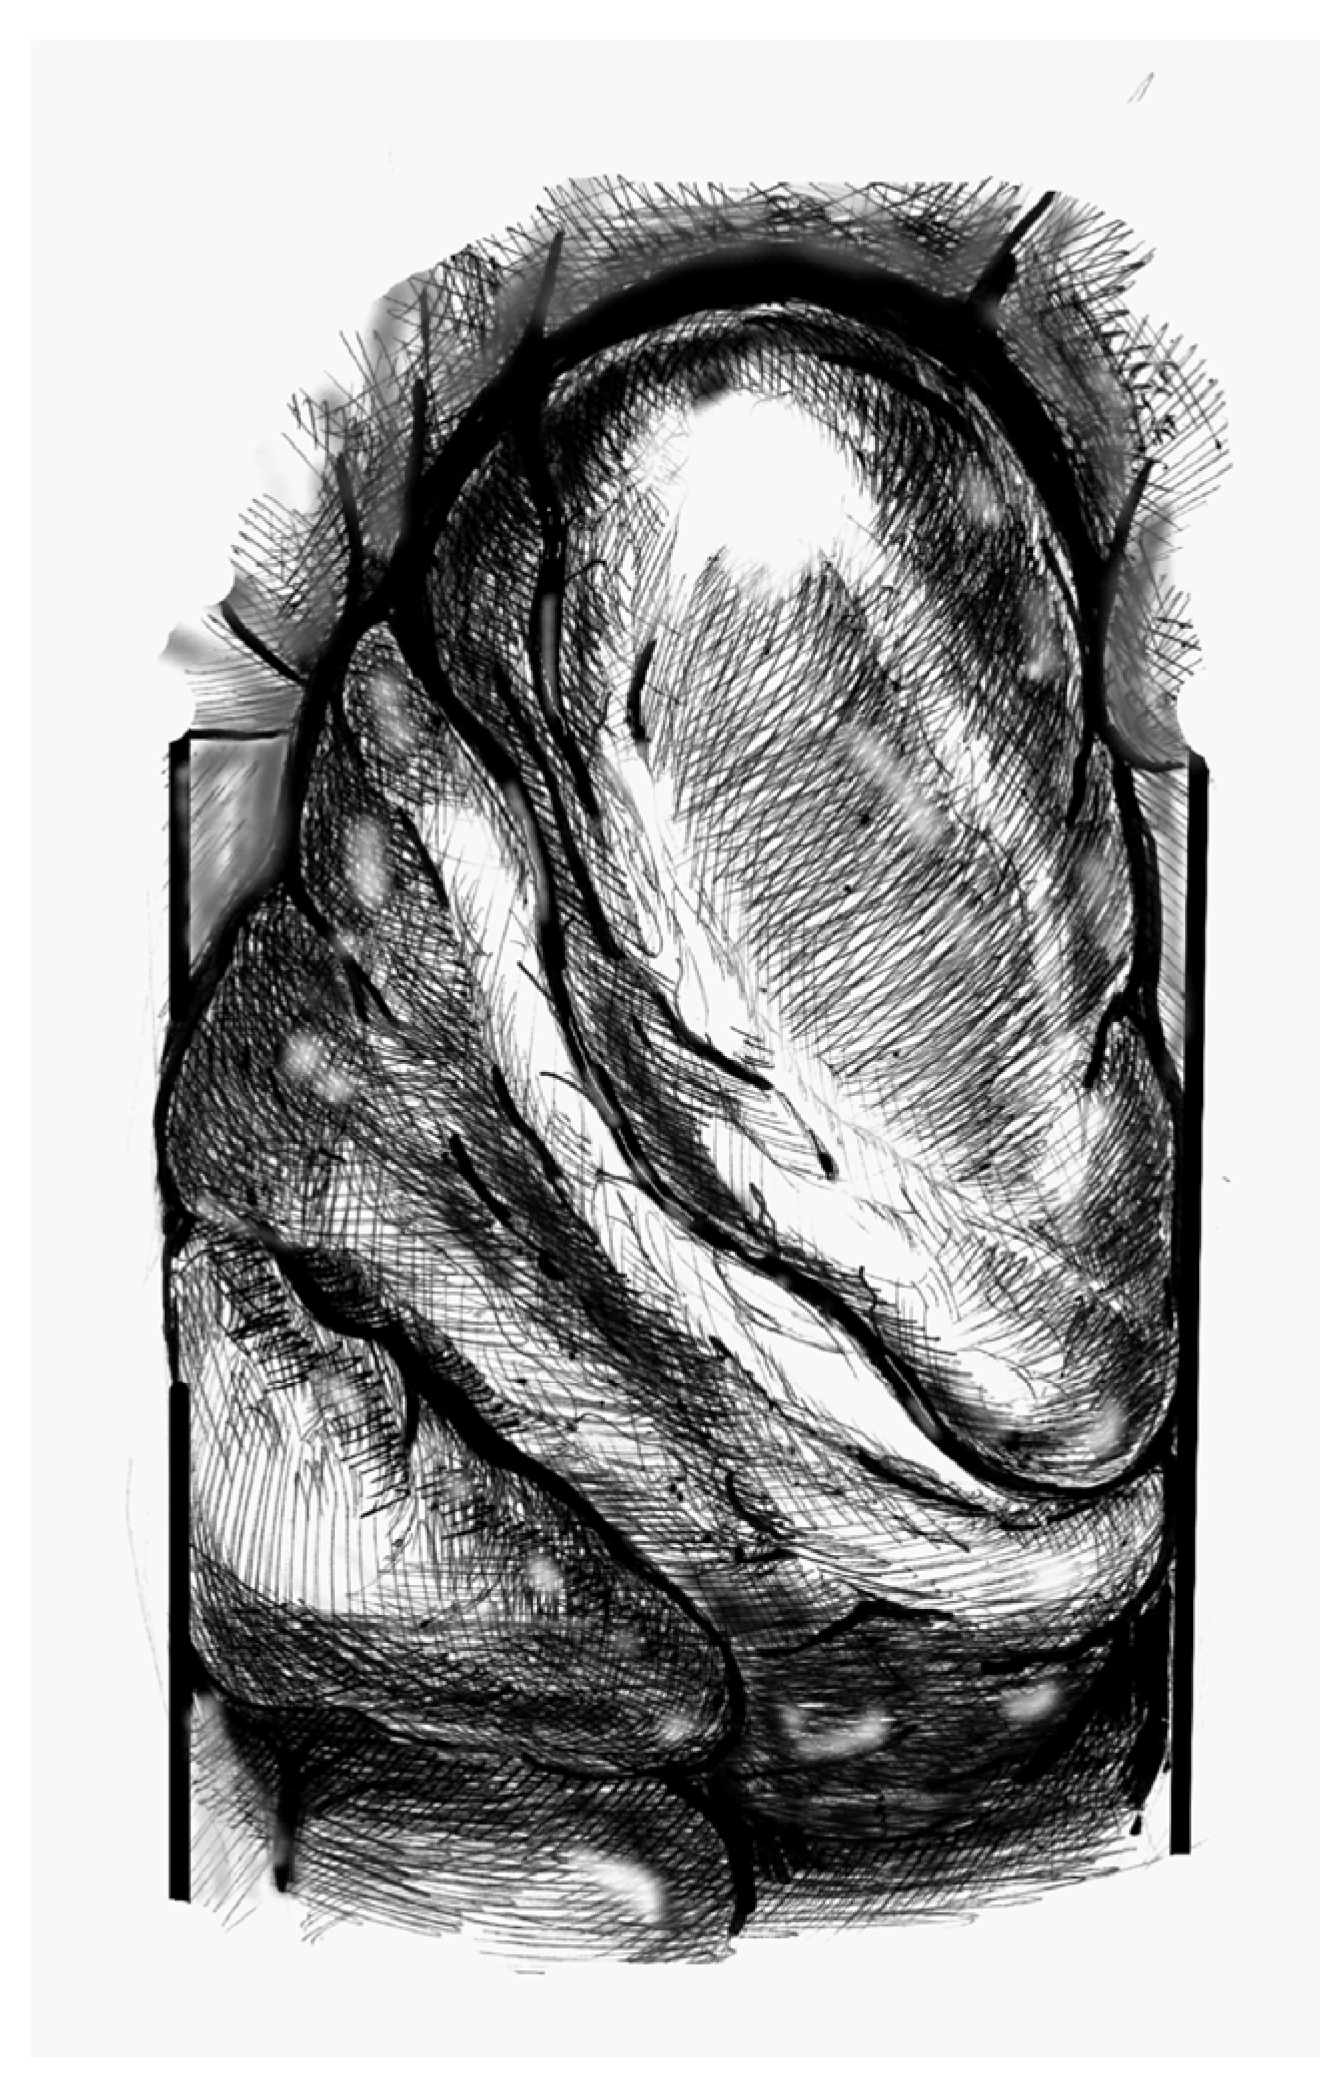

- Figure 1. Elevate the heart to expose the apex, then incise the epicardium. Maintain the trajectory towards the outflow tract/aortic valve to avoid deviating into the right ventricle (RV) or causing septal injury. Use transoesophageal echocardiography (TEE) at this stage to confirm the orientation.